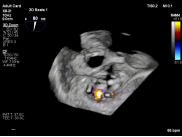

针对该病例特点,团队制定个体化诊疗策略,在穿刺位置、器械路径及夹持方式上进行精细设计。术中,团队优化房间隔穿刺高度与位置,匹配GAP结构特点;反复调整导向系统,确保器械垂直对准反流中心;通过多平面及三维TEE确认最佳夹持窗口;采用分步夹持策略,提高瓣叶抓取成功率,确保手术过程平稳。

【图片7-9:术中定位、夹持过程及术后效果图】

术后评估显示,患者二尖瓣反流由极重度明显降低至中度以下,血流动力学改善,手术取得良好效果